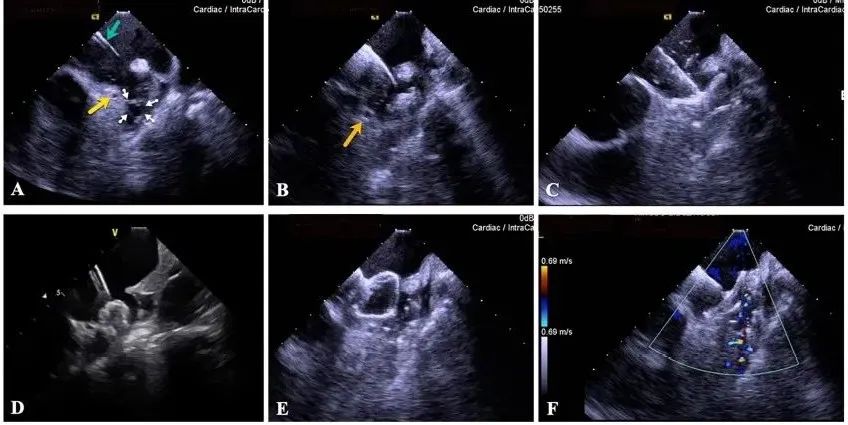

一種與心導(dǎo)管檢查相結(jié)合的超聲心動圖診斷新興技術(shù),通過將超聲探頭置于心腔內(nèi)部,發(fā)射并接收超聲信號,來精確獲取心臟解剖結(jié)構(gòu)、心臟血流動力學(xué)等信息的實時成像。與其他影像技術(shù)相比,ICE技術(shù)具有操作簡單、無輻射、安全性高、手術(shù)效率高、實用等優(yōu)勢,ICE在很大程度上有望取代經(jīng)食道超聲心動圖(TEE),成為電生理和結(jié)構(gòu)性心臟病領(lǐng)域的理想成像方式。

目前ICE技術(shù)已被應(yīng)用于左心耳封堵、房顫射頻消融、二尖瓣成形、房間隔缺損封堵等多種心臟介入手術(shù),應(yīng)用場景主要圍繞臟電生理、結(jié)構(gòu)性心臟病等領(lǐng)域,目前以電生理應(yīng)用為主。數(shù)據(jù)顯示,我國結(jié)構(gòu)性心臟病介入器械市場規(guī)模已從2017年的4億元增長至2021年的20億元,年復(fù)合增長率達48.3%;預(yù)計到2025年,該市場規(guī)模將達到104億元,可以預(yù)見ICE市場規(guī)模也將同步高速增長,未來市場發(fā)展空間廣闊。

心腔內(nèi)超聲(ICE)技術(shù)壁壘極高,國內(nèi)主要廠商核心部件仍舊為進口,集成了超聲和圖像處理最前端技術(shù),包括超聲探頭、線纜、軟件成像算法等,是當(dāng)前內(nèi)窺超聲方向最具挑戰(zhàn)的領(lǐng)域。ICE的應(yīng)用經(jīng)歷了2D平面成像、3D三維立體成像、以及4D的實時三維立體成像階段。